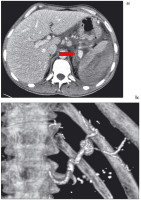

Abbildung 6: a) Pankreaspseudozysten mit Milzarterienaneurysma (→). b) Die Gefäßrekonstruktion zeigt das Pseudoaneurysma noch deutlicher sowie die distal davon nur schmächtige A. lienalis.

Keywords: chronische PankreatitisComputertomographieCTGastroenterologie

Abbildung 7: a) Die Milz ist durch ein geschichtetes, subkapsuläres, ventral rupturiertes Hämatom massiv vergrößert (CT 20.1. 2007, venöse Phase). Gegenüber der Leber ist die Durchblutung der Milz vermindert. Das Pseudoaneurysma (→) ist größenprogredient. b) Die Gefäßrekonstruktion zeigt das Pseudoaneurysma und die distal davon nur noch dünne A. lienalis.